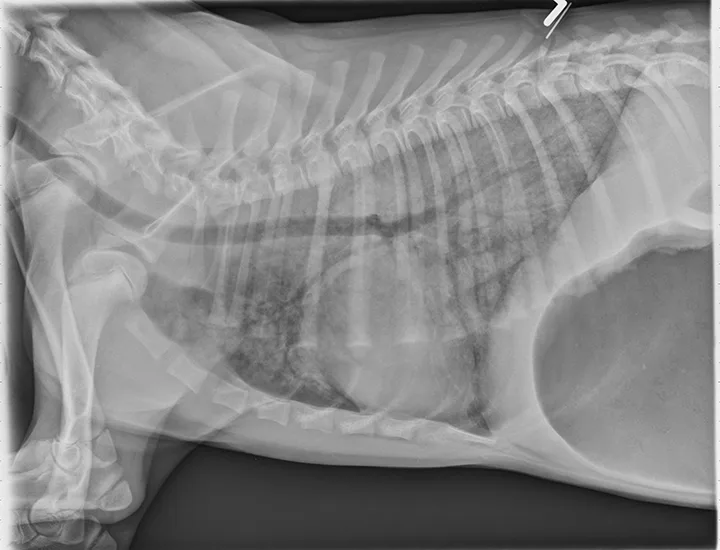

Lateral thoracic x-ray of a dog showing diffuse opacity of lung parenchyma.

Thoracic radiographs can appear normal initially, but changes to the pulmonary parenchyma may become more apparent within 24 to 72 hours as respiratory injury progresses. Evidence of patchy pulmonary edema with bronchial, interstitial, or alveolar patterns may be observed [Figures 1 and 2].6,13,16,19 Right middle lung lobe consolidation and pleural effusion in cats have been reported.6,13,16 An alveolar pattern may be seen on serial radiographs in patients that develop secondary bacterial pneumonia.6

FIGURE 1

A severe, diffuse patchy interstitial-to-alveolar pattern, more severe in the mid-to-caudodorsal lung fields, in a dog with smoke inhalation injury after a house fire